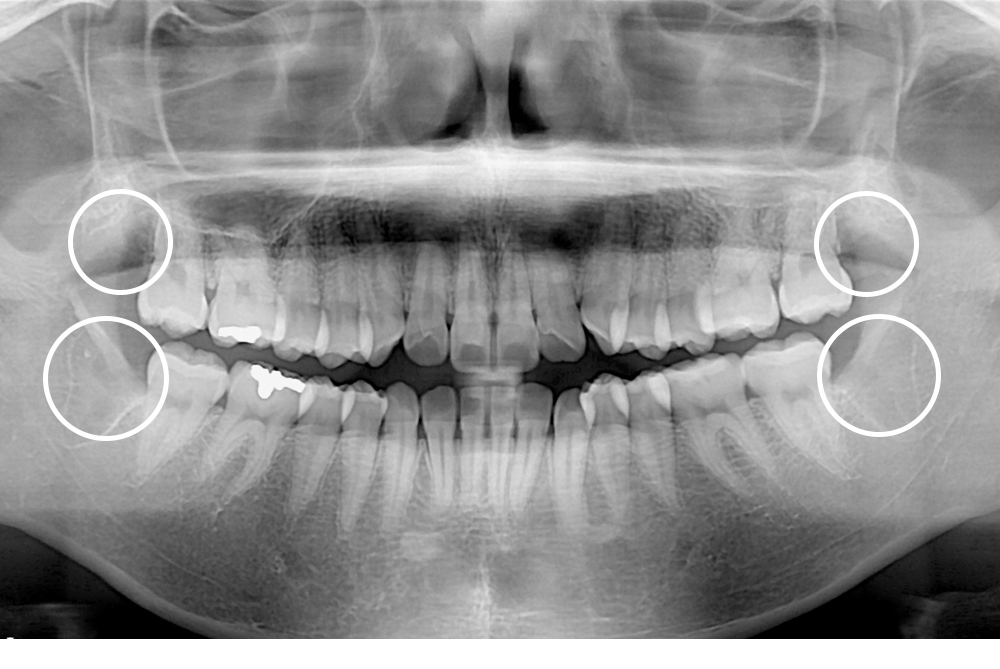

[사랑니] 매복 사랑니 발치

치료전 : 2020-07-13

세종치과는 구강악안면외과학 박사이신 원장님이 발치하는 치과입니다.